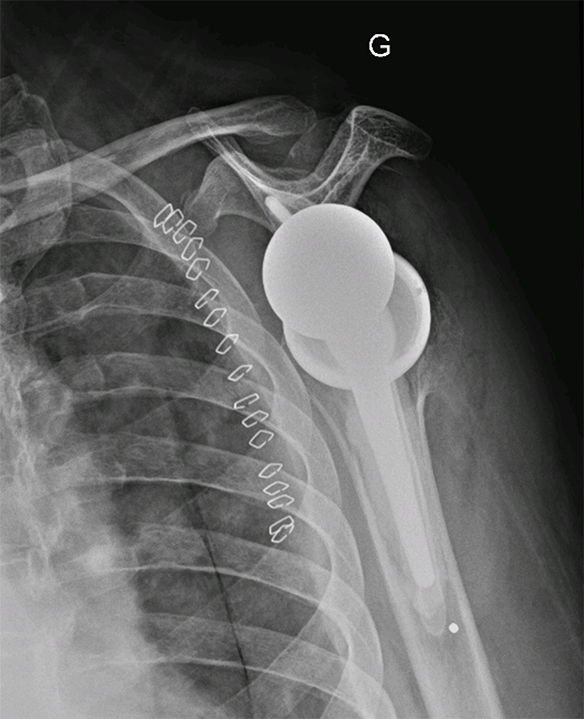

L’intervention se fait par une voie d’abord se situant à l’avant de l’épaule. L’abord de l’articulation nécessite une section du tendon du sous-scapulaire, qui sera réparé en fin d’intervention. Le chirurgien sectionne la tête humérale pour préparer l’os à l’aide de râpe et de compacteur pour positionner la tige humérale. Il prépare ensuite la glène de l’omoplate pour y implanter l’autre versant prothétique qui sera fixé dans l’os avec des vis et un plot recouvert d’un revêtement permettant une bonne tenue osseuse. Le chirurgien dispose de plusieurs tailles pour les implants qui sont adaptés à la morphologie de chaque patient. En fin d’intervention, le chirurgien positionnera un drain ou redon qui limitera la survenue d’un hématome post opératoire et qui sera retiré à 48 heures.

Prothèse épaule inversée - Dr Dumoulin